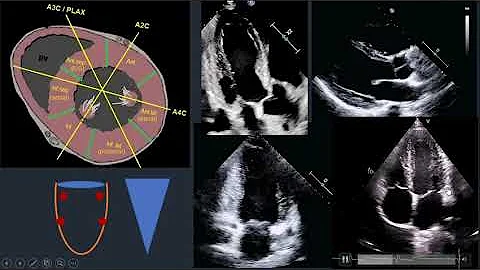

Shorts Regional Wall Motion Abnormality (RWMA) on Echocardiography.